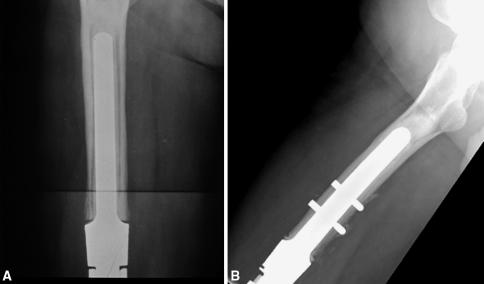

骨肿瘤保肢治疗中骨水泥型股骨远端假体的应用:模块化假体与定制假体的生存率比较。

Cemented distal femoral endoprostheses for musculoskeletal tumor: improved survival of modular versus custom implants.

RESULTS

Kaplan-Meier analysis revealed overall 10-, 20-, and 25-year implant survival rates of 77%, 58%, and 50%, respectively, using revision of the stemmed components as an end point. The 85 modular components had a greater 15-year survivorship than the 101 custom-designed implants: 93.7% versus 51.7%, respectively. Thirty-five stemmed components (18.8%) were revised for aseptic loosening in 22 patients, implant fatigue fracture in 10, infection in two, and local recurrence in one.

CONCLUSIONS

Cemented modular rotating-hinge distal femoral endoprostheses demonstrated improved survivorship compared with custom-casted implants during this three-decade experience. Patients with low-grade disease and long-term survivors of high-grade localized disease should expect at least one or more revision procedures in their lifetime.